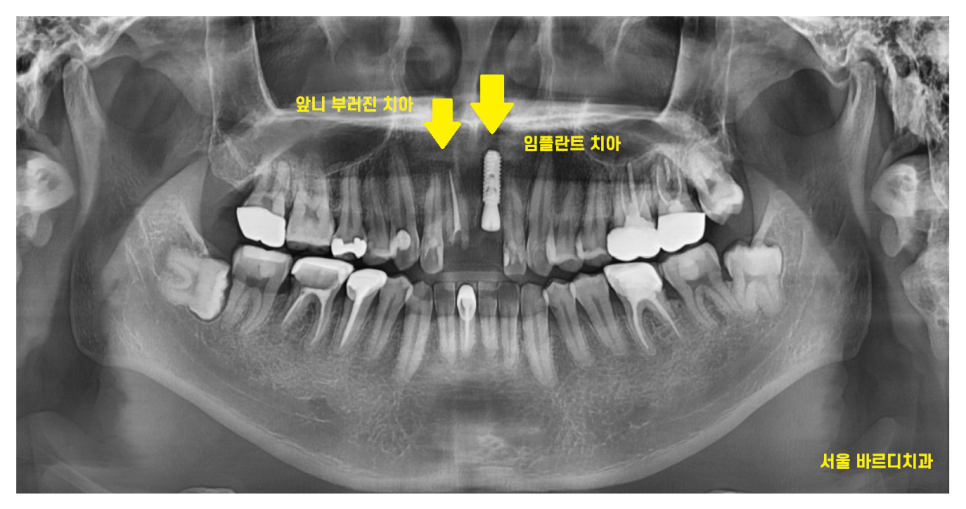

큰 x-ray로 확인을 해보니..

여지없이 신경치료가 되어 있는 상황

치아 1개가 또 부러졌네요.

잇몸 뼈 안쪽으로 뿌리만 남아있는 상황입니다.

남아있는 치아가 충치도 있고

부러진 양도 많고

상태가 영... 안좋네요ㅠㅠ